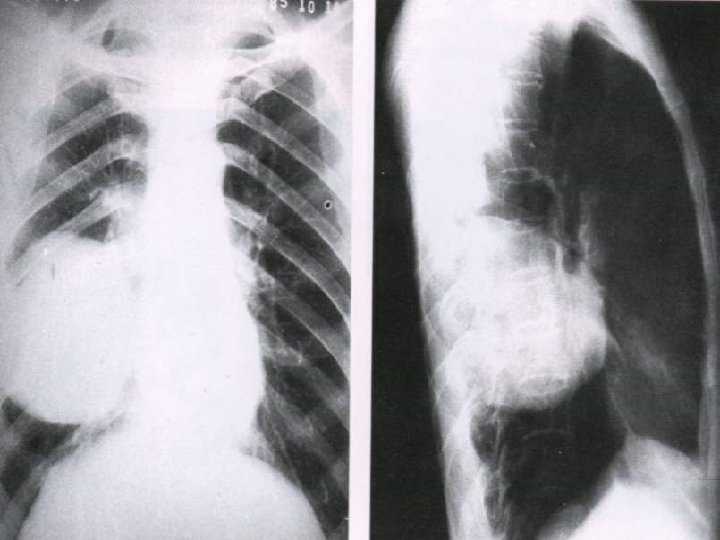

DIAGNOSIS 1. 2. 3. 4. 5. 6. 7. 8. 9. 10. x-ray examination. CT chest. MRI chest cytological examination of sputum. Bronchoscopic examination. Mediastinoscopy. Needle biopsy. Percutaneous transthoracic Lymph nodes biopsy. Supraclavicular, cervical, axillary. Pleural effusion examination. Thoracic exploration.

(Obstructive atelectasis)